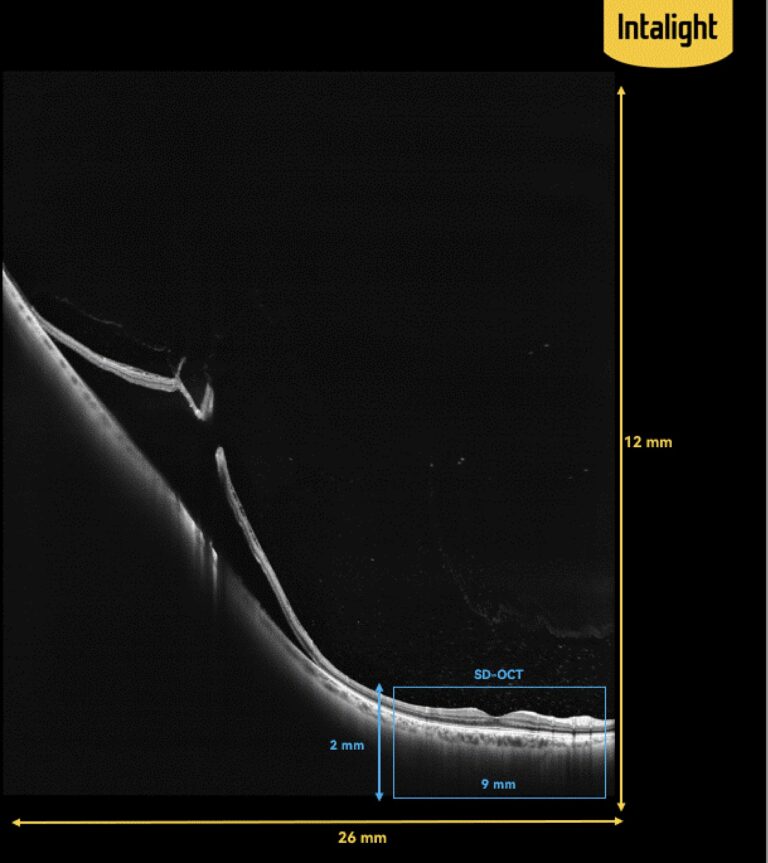

Powered by Super Depth technology, DREAM OCT expands imaging depth from 2 mm to 12 mm. This is six times greater than that of a traditional SD-OCT, which you are accustomed to 🙌.

This could help you to find retinal holes and detachment in the periphery.

Moreover, with the ultra-widefield lens, an OCTA image of 26 mm × 21 mm, equivalent to 130° in the intraocular angle, can be acquired with a single scan.